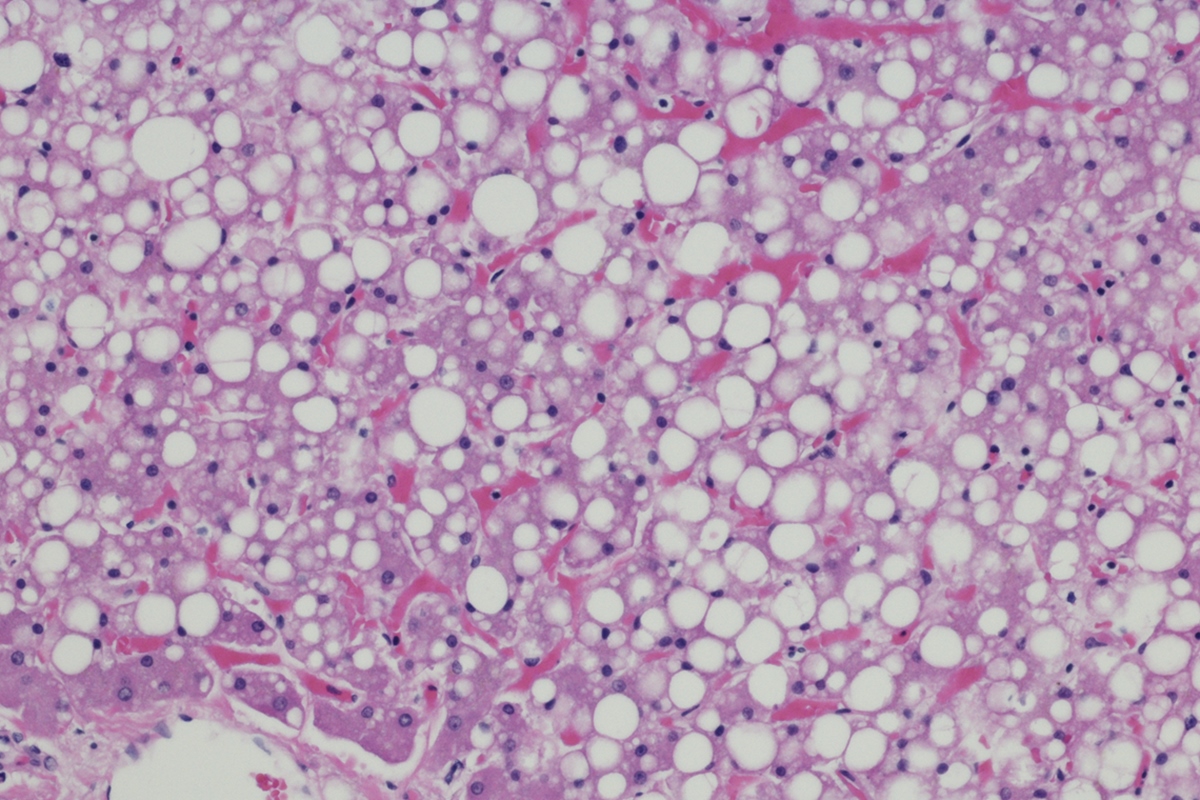

Tratamento e estilo de vida

Apesar de ser uma condição perigosa, a gordura no fígado não costuma ser tratada com medicamentos. A maneira mais simples de lidar com a esteatose é uma mudança do estilo de vida.

“Em geral, quando o paciente adota mudanças consistentes de estilo de vida – com alimentação equilibrada, perda de 7% a 10% do peso corporal e prática regular de exercícios – já é possível observar melhora significativa nas enzimas hepáticas e na quantidade de gordura no fígado em cerca de três a seis meses”, revela a gastro-hepatologista Natália Trevizoli, do Hospital Santa Lúcia Sul, em Brasília.

Ilustração mostra um fígado cheio de gordura e com moléculas de glicose. Gordura no fígado - MetrópolesA esteatose hepática, ou gordura no fígado, pode surgir em pessoas magras ou que se alimentam relativamente bem devido a outros fatores